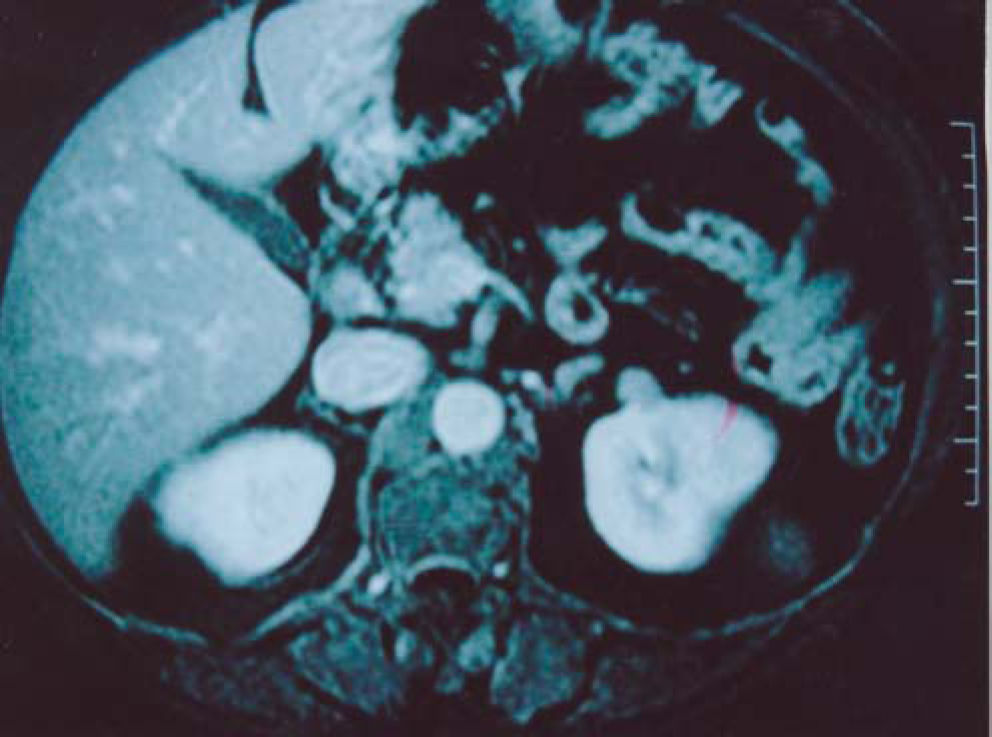

CASE REPORTA 52-year-old woman of mixed white and negro blood, suffering from diabetes mellitus, arterial hypertension, and stable angina, was undergoing treatment with enalapril, atenolol, hydrochlorothiazide, metformin, and aspirin. There was no significant familial history of neoplastic diseases. The physical examination was unremarkable. The complete blood count, blood biochemical values, and urinalysis were normal. She underwent magnetic resonance for assessment of the renal vessels, which were normal, though, incidentally, a 2-cm solid lesion was found in the left kidney (Fig. 1). The rest of the abdominal cavity was normal.